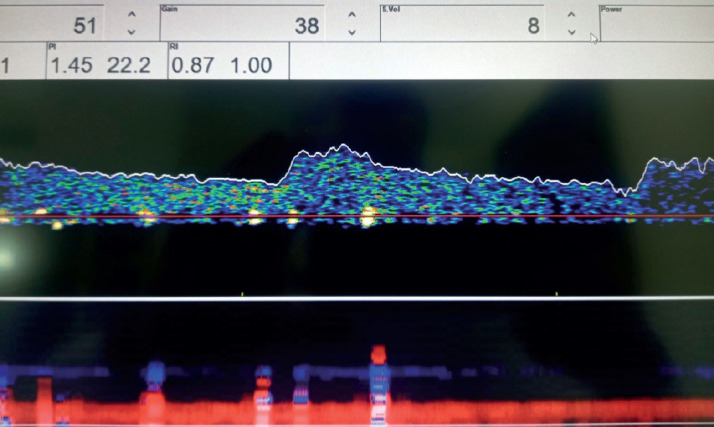

Background: Carotid atherosclerosis is often mentioned as one of the main causes of stroke. Currently, embolization is considered the most common mechanism that causes ischemic strokes due to atherosclerotic lesions in the carotid artery. Transcranial Doppler (TCD) ultrasound provides relatively inexpensive, noninvasive, real-time measurement of blood flow characteristics and cerebrovascular hemodynamics within brain arteries. The pulsatile index measured by transcranial Doppler is a parameter that indicates the degree of elasticity of the blood vessels of the brain.

Objective: The aim of this study is to determine the relationship between the value of the pulsatile index of the middle cerebral artery and the basilar artery in patients with carotid stenosis using transcranial Doppler and the value of the pulsatile index in relation to the degree of carotid stenosis.

Methods: The study involved a total of 140 patients examined at the Color Doppler and Transcranial Doppler Department of the Neurology Department of the General Hospital "Prim Dr. Abdulah Nakas" Sarajevo The patients were divided into two groups. The research was conducted in the General Hospital "Prim. dr. Abdulah Nakas" in Sarajevo at the Department for Color Doppler and Transcranial Doppler of the Department of Neurology and included patients examined in the period from February 2022 to December 2022. All patients underwent extracranial Doppler of the carotid arteries and transcranial Doppler of the middle cerebral artery and basilar artery.

Results: The mean values of PI in ACM in the total sample were statistically significantly lower in patients with stenosis up to 50% compared to the average in patients with stenosis over 50%. Average values of PI in AB in the total sample were statistically significantly lower in patients with stenosis up to 50% compared to the mean values in patients with stenosis over 50%.

Conclusion: Transcranial Doppler findings showed an increased pulsatile index in patients who had carotid stenosis greater than 50% compared to patients with mild carotid stenosis. The study showed that in clinical work it would be necessary to introduce the pulsatile index as an indispensable neurosonological parameter that would be included in the findings of the transcranial Doppler and thus objectify the potential risk of a cerebrovascular ischemic event.